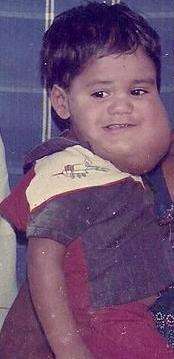

| A child with cystic hygroma | |

Same patient as on image at top - After 1st Surgery

Same patient as on image at top - After 1st Surgery Same patient - After 4 Surgeries